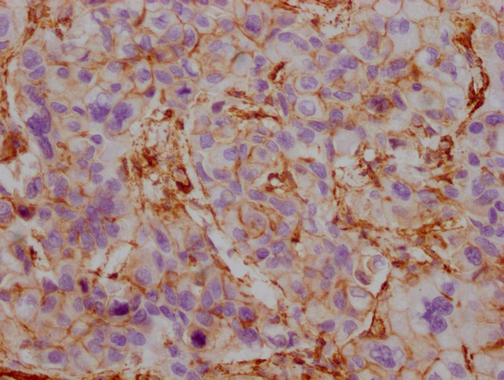

Human heart tissue

1:100